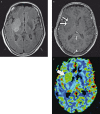

Our goal was to determine whether relative cerebral blood volume (rCBV) can serve as an adjunct to histopathologic grading in the assessment of gliomas, with the hypothesis that rCBV can predict two-year survival. We evaluated 29 newly diagnosed gliomas (13 WHO grade II, seven grade III, nine grade IV; 17 astrocytomas, 12 oligodendroglial tumors). Dynamic susceptibility-weighted contrast-enhanced perfusion MR images and CBV maps were obtained. rCBVmax measurements (maximum tumor CBV/contralateral normal tissue CBV) and progression-free survival (PFS) were recorded. Receiver operating characteristic curves and Kaplan-Meier survival curves were calculated for rCBVmax and histologic grade. rCBVmax measurements differed between gliomas without (2.38 +/- 1.22) and with progression (5.57 +/- 2.84) over two years. The optimal rCBVmax cut-off value to predict progression was 2.95. rCBVmax < 2.95 was a significant predictor of two-year PFS, almost as accurate as WHO grade II. In the pure astrocytoma subgroup, the optimal rCBVmax cut-off value to predict progression was 2.85. In this group rCBVmax < 2.85 was a significant predictor of two-year PFS, an even better predictor of two-year PFS than WHO grade II. rCBVmax can be used to predict two-year PFS in patients with gliomas, independent of pathologic findings, especially in tumors without oligodendroglial components.